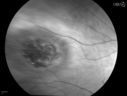

Chorodial Melanoma1230 views80 year old male came in for retinal evaluation and presented with a melanoma.Jun 10, 2014